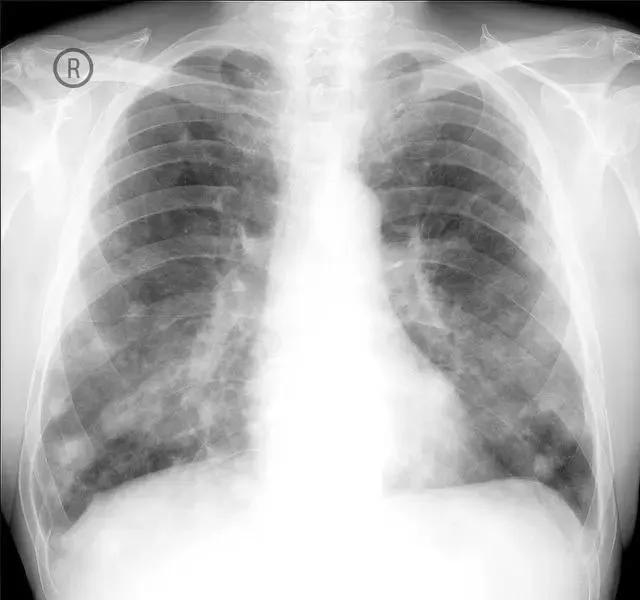

感冒引起的肺部感染